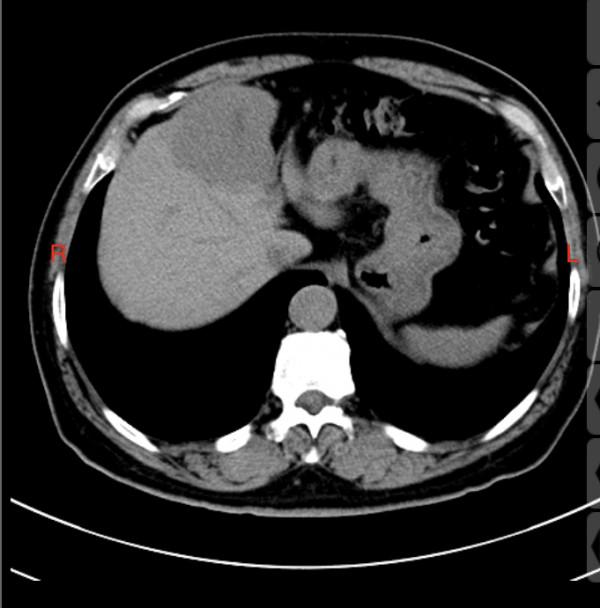

在我的督促下,王老師還是來醫院進行了抽血化驗,這次的AFP結果直接驚呆了我,達到了1800,看來大事不妙。趕緊和王老師的家人聯絡,帶他進行了CT檢查。發現肝臟的巨大腫塊,原發性肝細胞性肝癌基本確診。

從2018年的AFP輕微升高,到現在的巨塊型肝癌,3年的時間。

進行了手術治療,切除了半個肝臟,切除了膽囊,據手術醫生說,腫瘤包膜相對完整,沒有轉移的徵象。